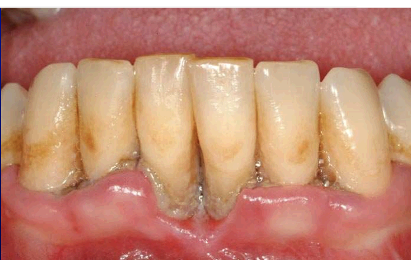

21

Q

what is this

A

necrotising periodontitis